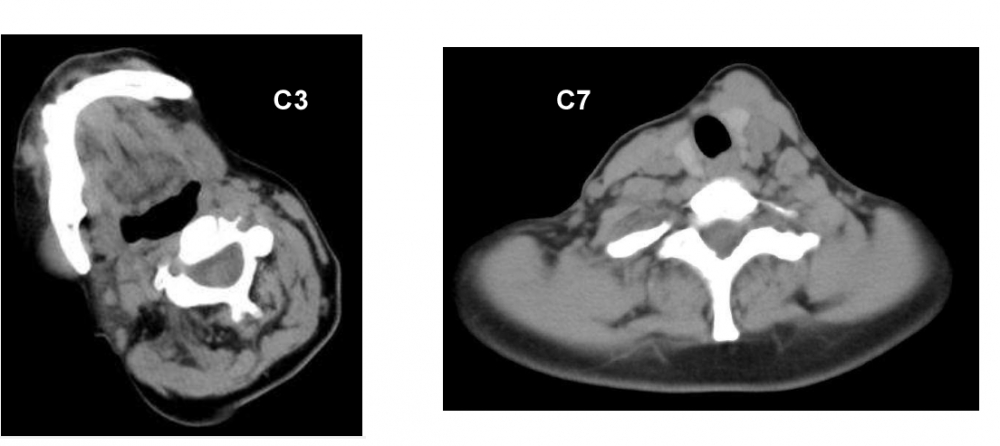

CT at levels C3 and C7 (note the C3 level is identified by the mandible being visible on the image)

At C3 the cervical vertebrum is in line with the skull, and away from C7

CT scan in this patient with torticollis shows that C1 and C2 are rotated, whereas C7 is straight. Rotation therefore occurs between C3 and C7; only muscles acting on the cervical spine are affected.